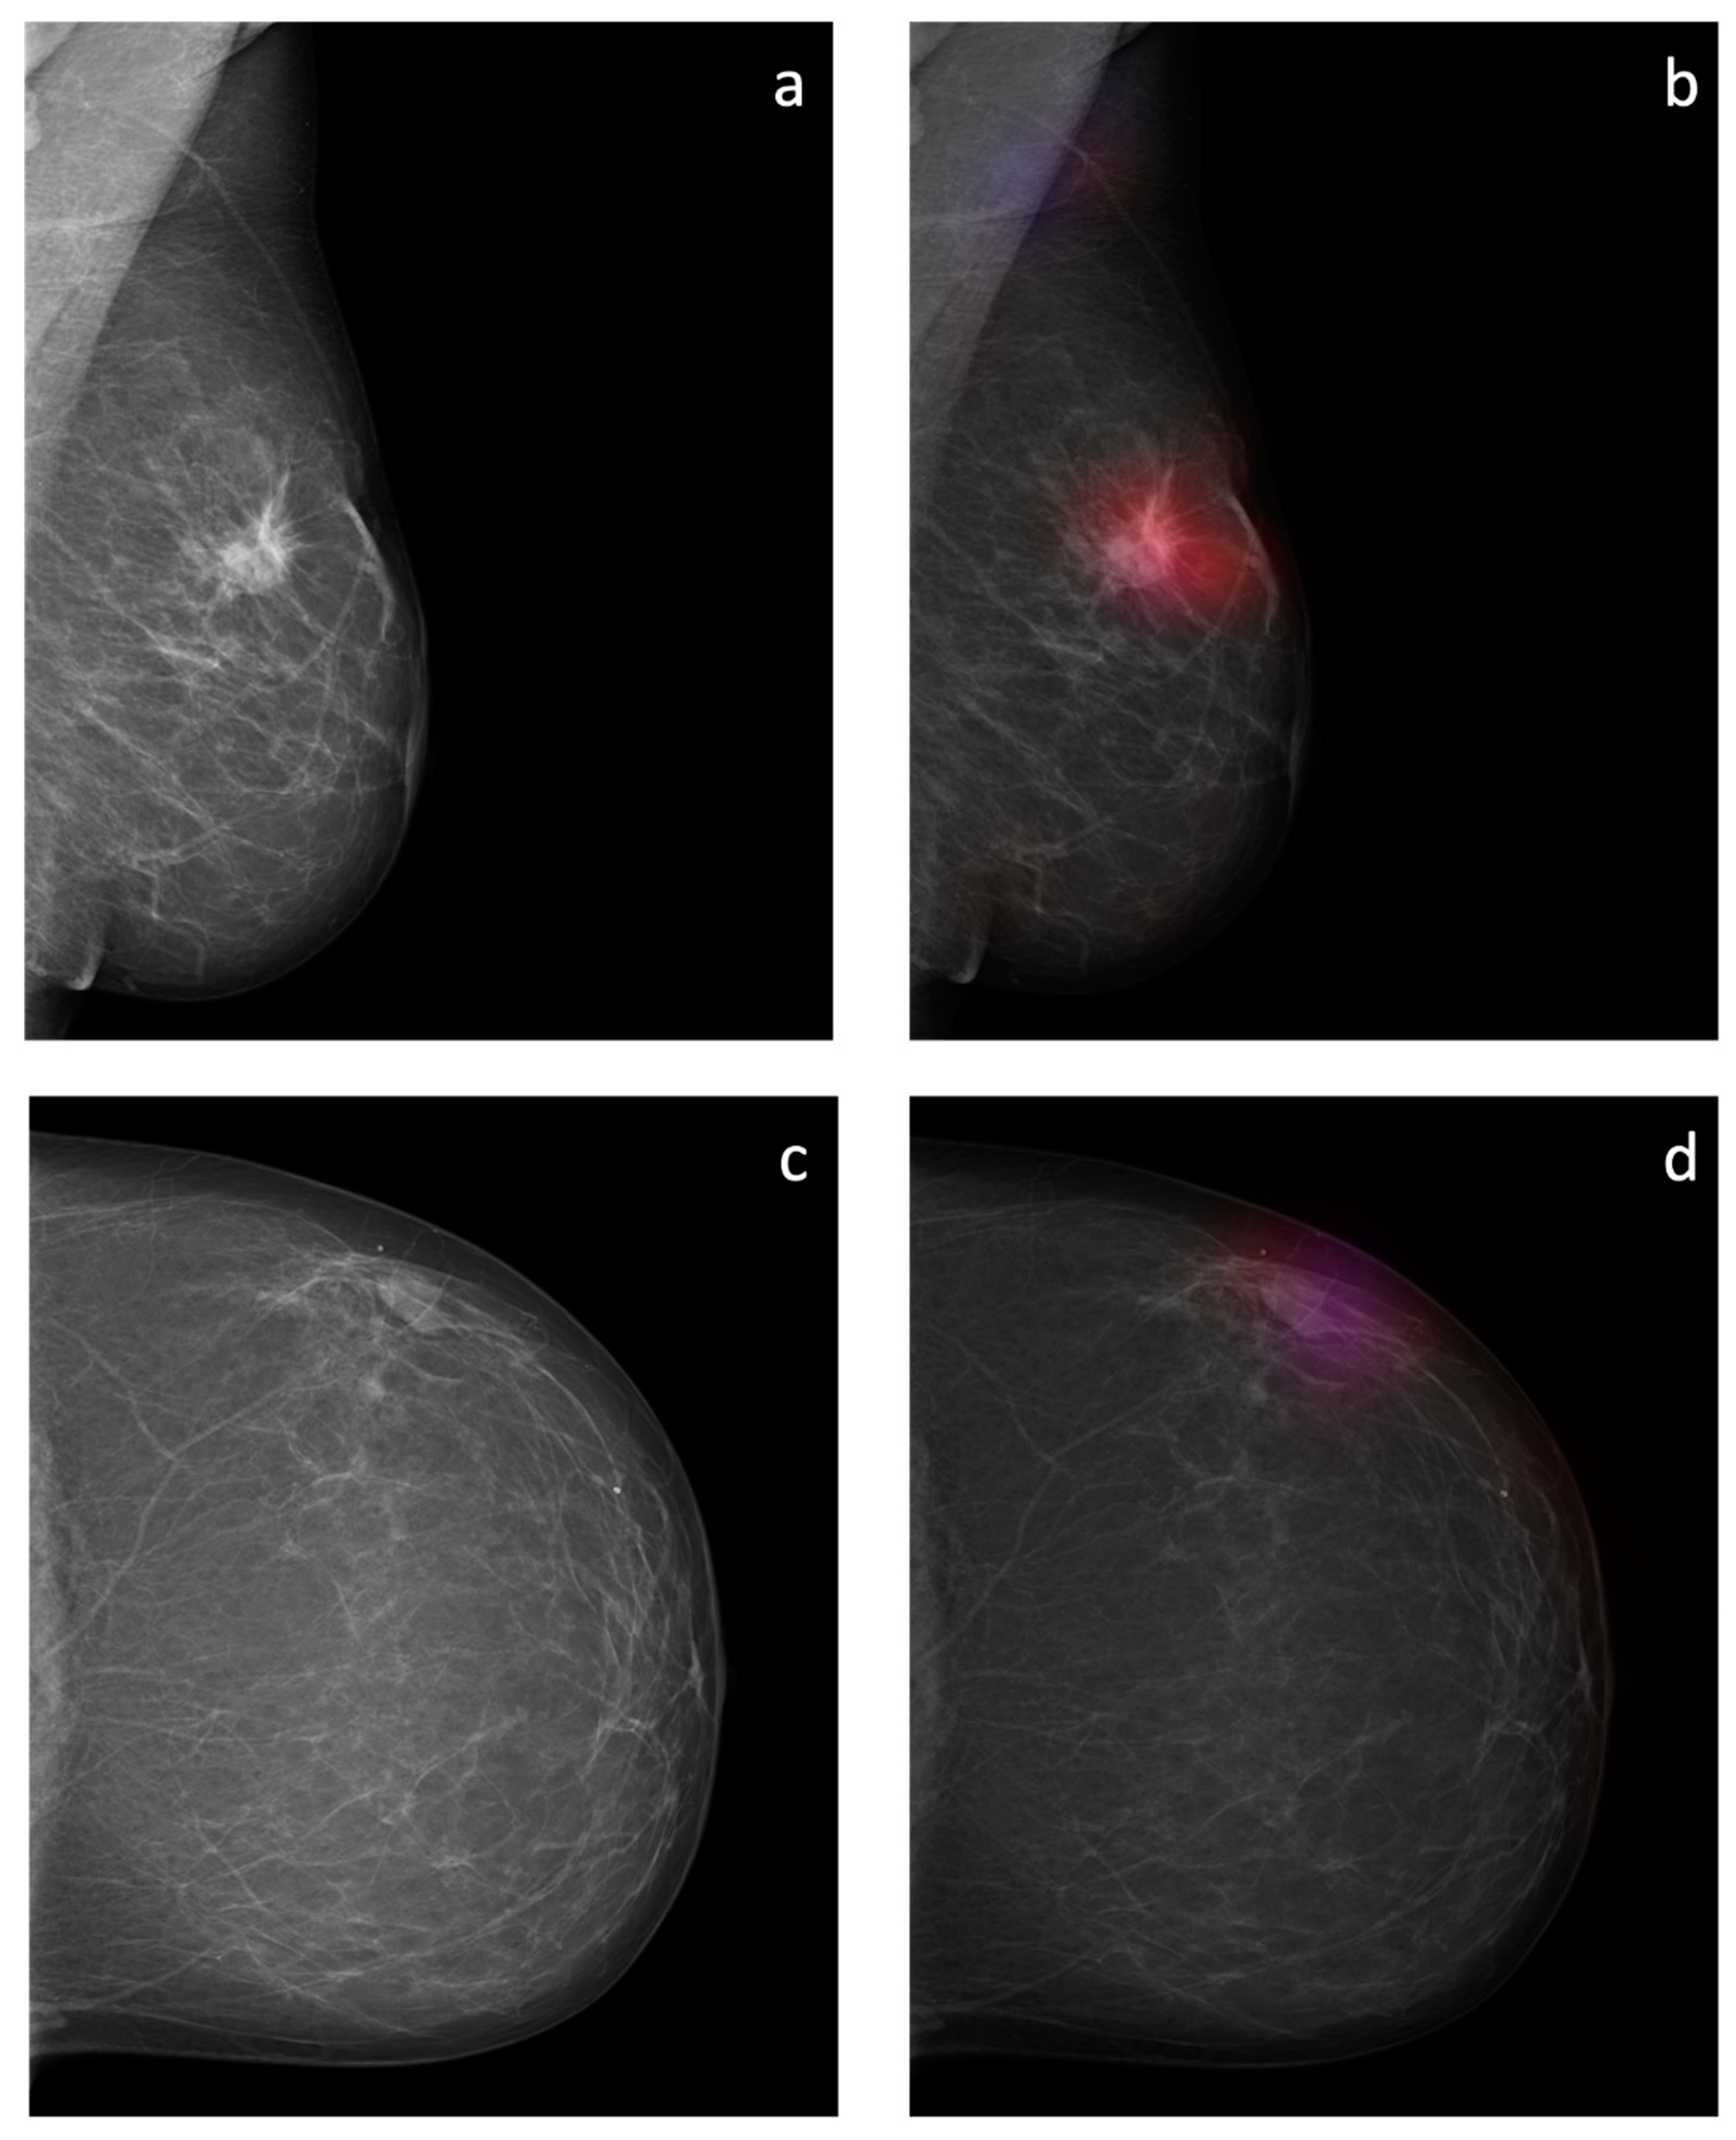

Figure 8. Overlay images of the calculated probability maps (b,d) created by the sliding window approach and the corresponding mammographic images (a,c) of two patients from the test dataset. In (a,b), a suspicious soft tissue opacity is highlighted in red. An area of denser tissue in the left axilla is correctly highlighted as a healthy tissue in blue. In (c,d), a probably benign soft tissue opacity is highlighted in purple.

3.3. Probability Maps

The sliding window approach was able to correctly detect the areal distribution of the suspicious soft tissue opacity. Excellent image quality could be obtained. Examples of probability maps are shown in (Figure 8).